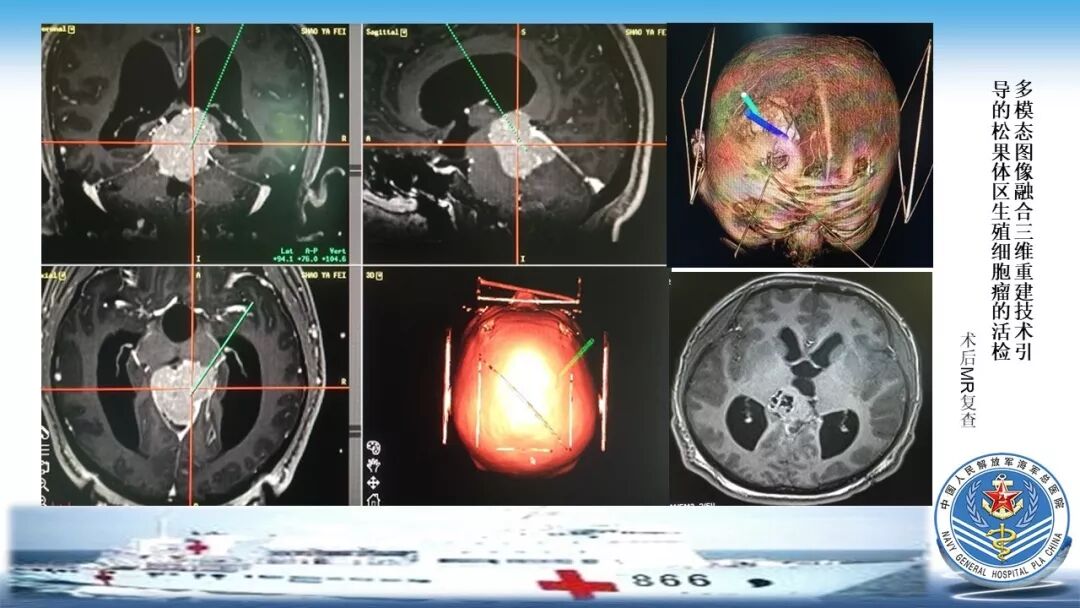

立体定向活检在脑干中线病变精准诊断中的作用

今天为大家带来的是中国人民解放军总医院第六医学中心(原中国人民解放军海军总医院)王亚明、于新、张剑宁带来的精彩课题分享:立体定向活检在脑干中线病变精准诊断中的作用,欢迎观看、阅读!